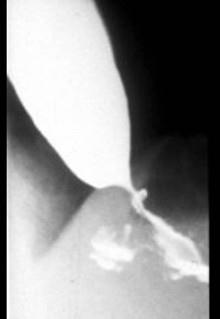

问题 患者,女性,50岁,进行性吞咽困难半年,现仅能进食水,入院行X线钡餐检查,结果如图所示,最可能的诊断是 ( )

选项 A、食管癌 B、以上均不正确 C、食管平滑肌瘤 D、贲门失弛症 E、食管憩室

答案 A